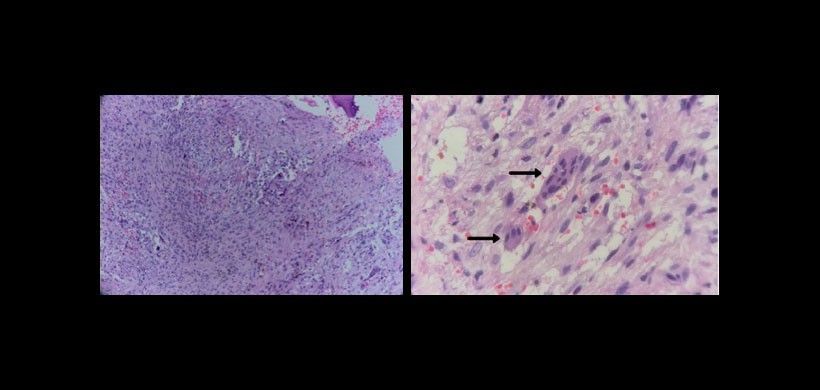

En el examen histológico, CGCL consiste en tejido celular fibroso con múltiples focos de hemorragia, agregados de células gigantes multinucleadas y, ocasionalmente, tejido óseo trabecular.

Figura 3: Tejido conectivo denso intraóseo con células fusiformes ovales y células gigantes, que indican un fibroma (granuloma) célula gigante central. Las células gigantes multinucleadas (flechas) rodeadas de conectivo intenso tejido y algunas células mesenquimales fusiformes, caracterizando el clásico marco histopatológico de las lesiones centrales de células gigantes, se puede encontrar. Tinción Hematoxilina y eosina.